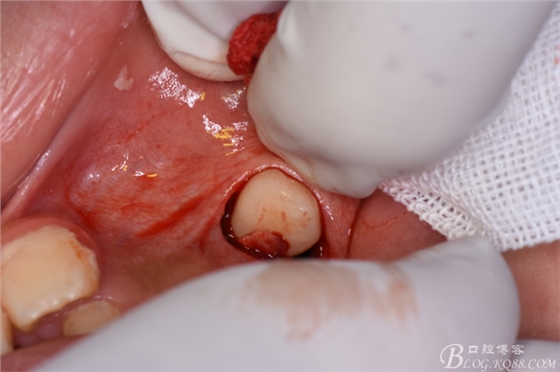

圖13.微創(chuàng)牙挺增隙、挺松23.

圖14. 23牙冠脫穎而出